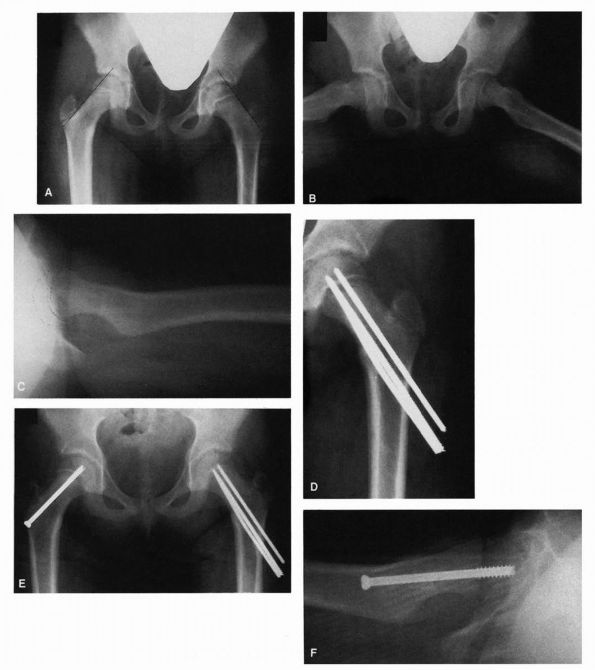

diagnostic sign and referred to the sensation palpated as the segno dello scotto. This palpable sensation has been likened to the femoral head gliding in and out of the acetabulum over a ridge. This ridge

of hypertrophied acetabular cartilage (Figure 15-1) was called the neolimbus

FIGURE 15-1.

In this full-term female infant with fairly severe dysplasia of the right hip, the acetabulum and femoral head are smaller on the right than on the left. Extending along the posterosuperior margin of the articular surface of the right dysplastic acetabulum is a shallow trough (T). At the anterior end of this trough is a bulge (B), and extending posteriorly along the inferior and anterior margin of the trough down to the inferior margin of the acetabulum is a ridge (R) that separates the primary acetabulum inferiorly and anteriorly from the trough and the rest of the secondary acetabulum superiorly and posteriorly. (Ponseti IV. Morphology of the acetabulum in congenital dislocation of the hip: gross, histological and roentgenographic studies. J Bone Joint Surg 1978;60A:586-599) |

varying degrees of capsular laxity and the thickening of the acetabular

cartilage in the superior, posterior, and inferior aspects of the

acetabulum. This thickening in the cartilage was called neolimbus by Ortolani (see Figure 15-1). It is the